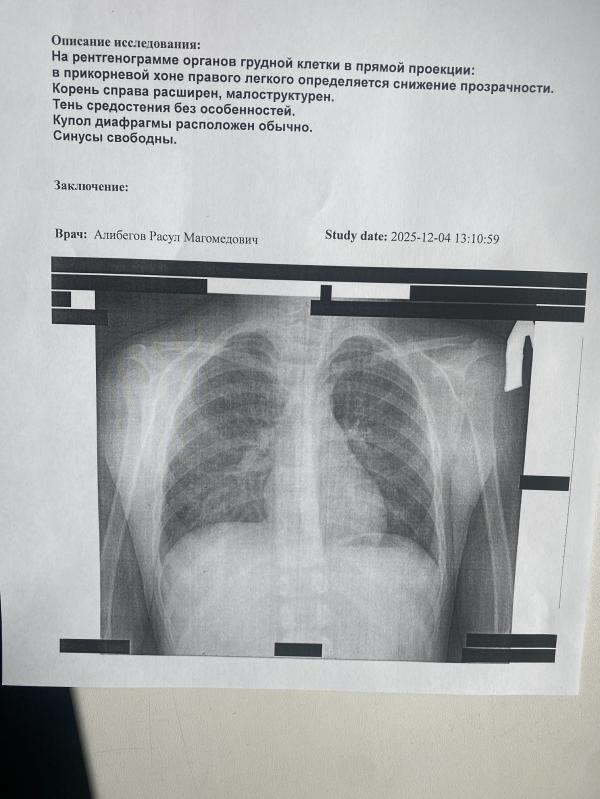

Как расшифровать анализ ребенка: есть ли бронхит или нет?

Девочки помогите расшифровать есть ли бронхит у ребенка или нет? Нашего врача как на зло нет